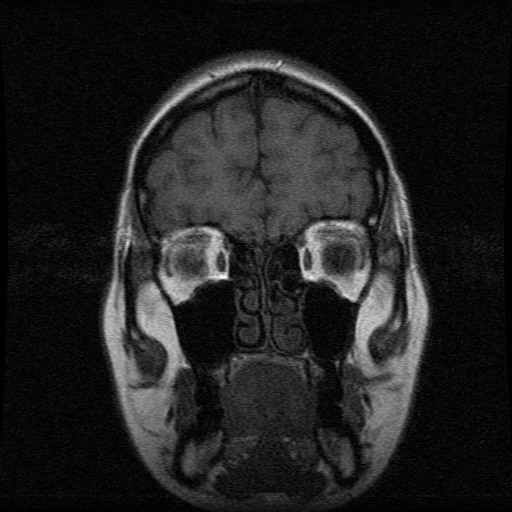

Schedel